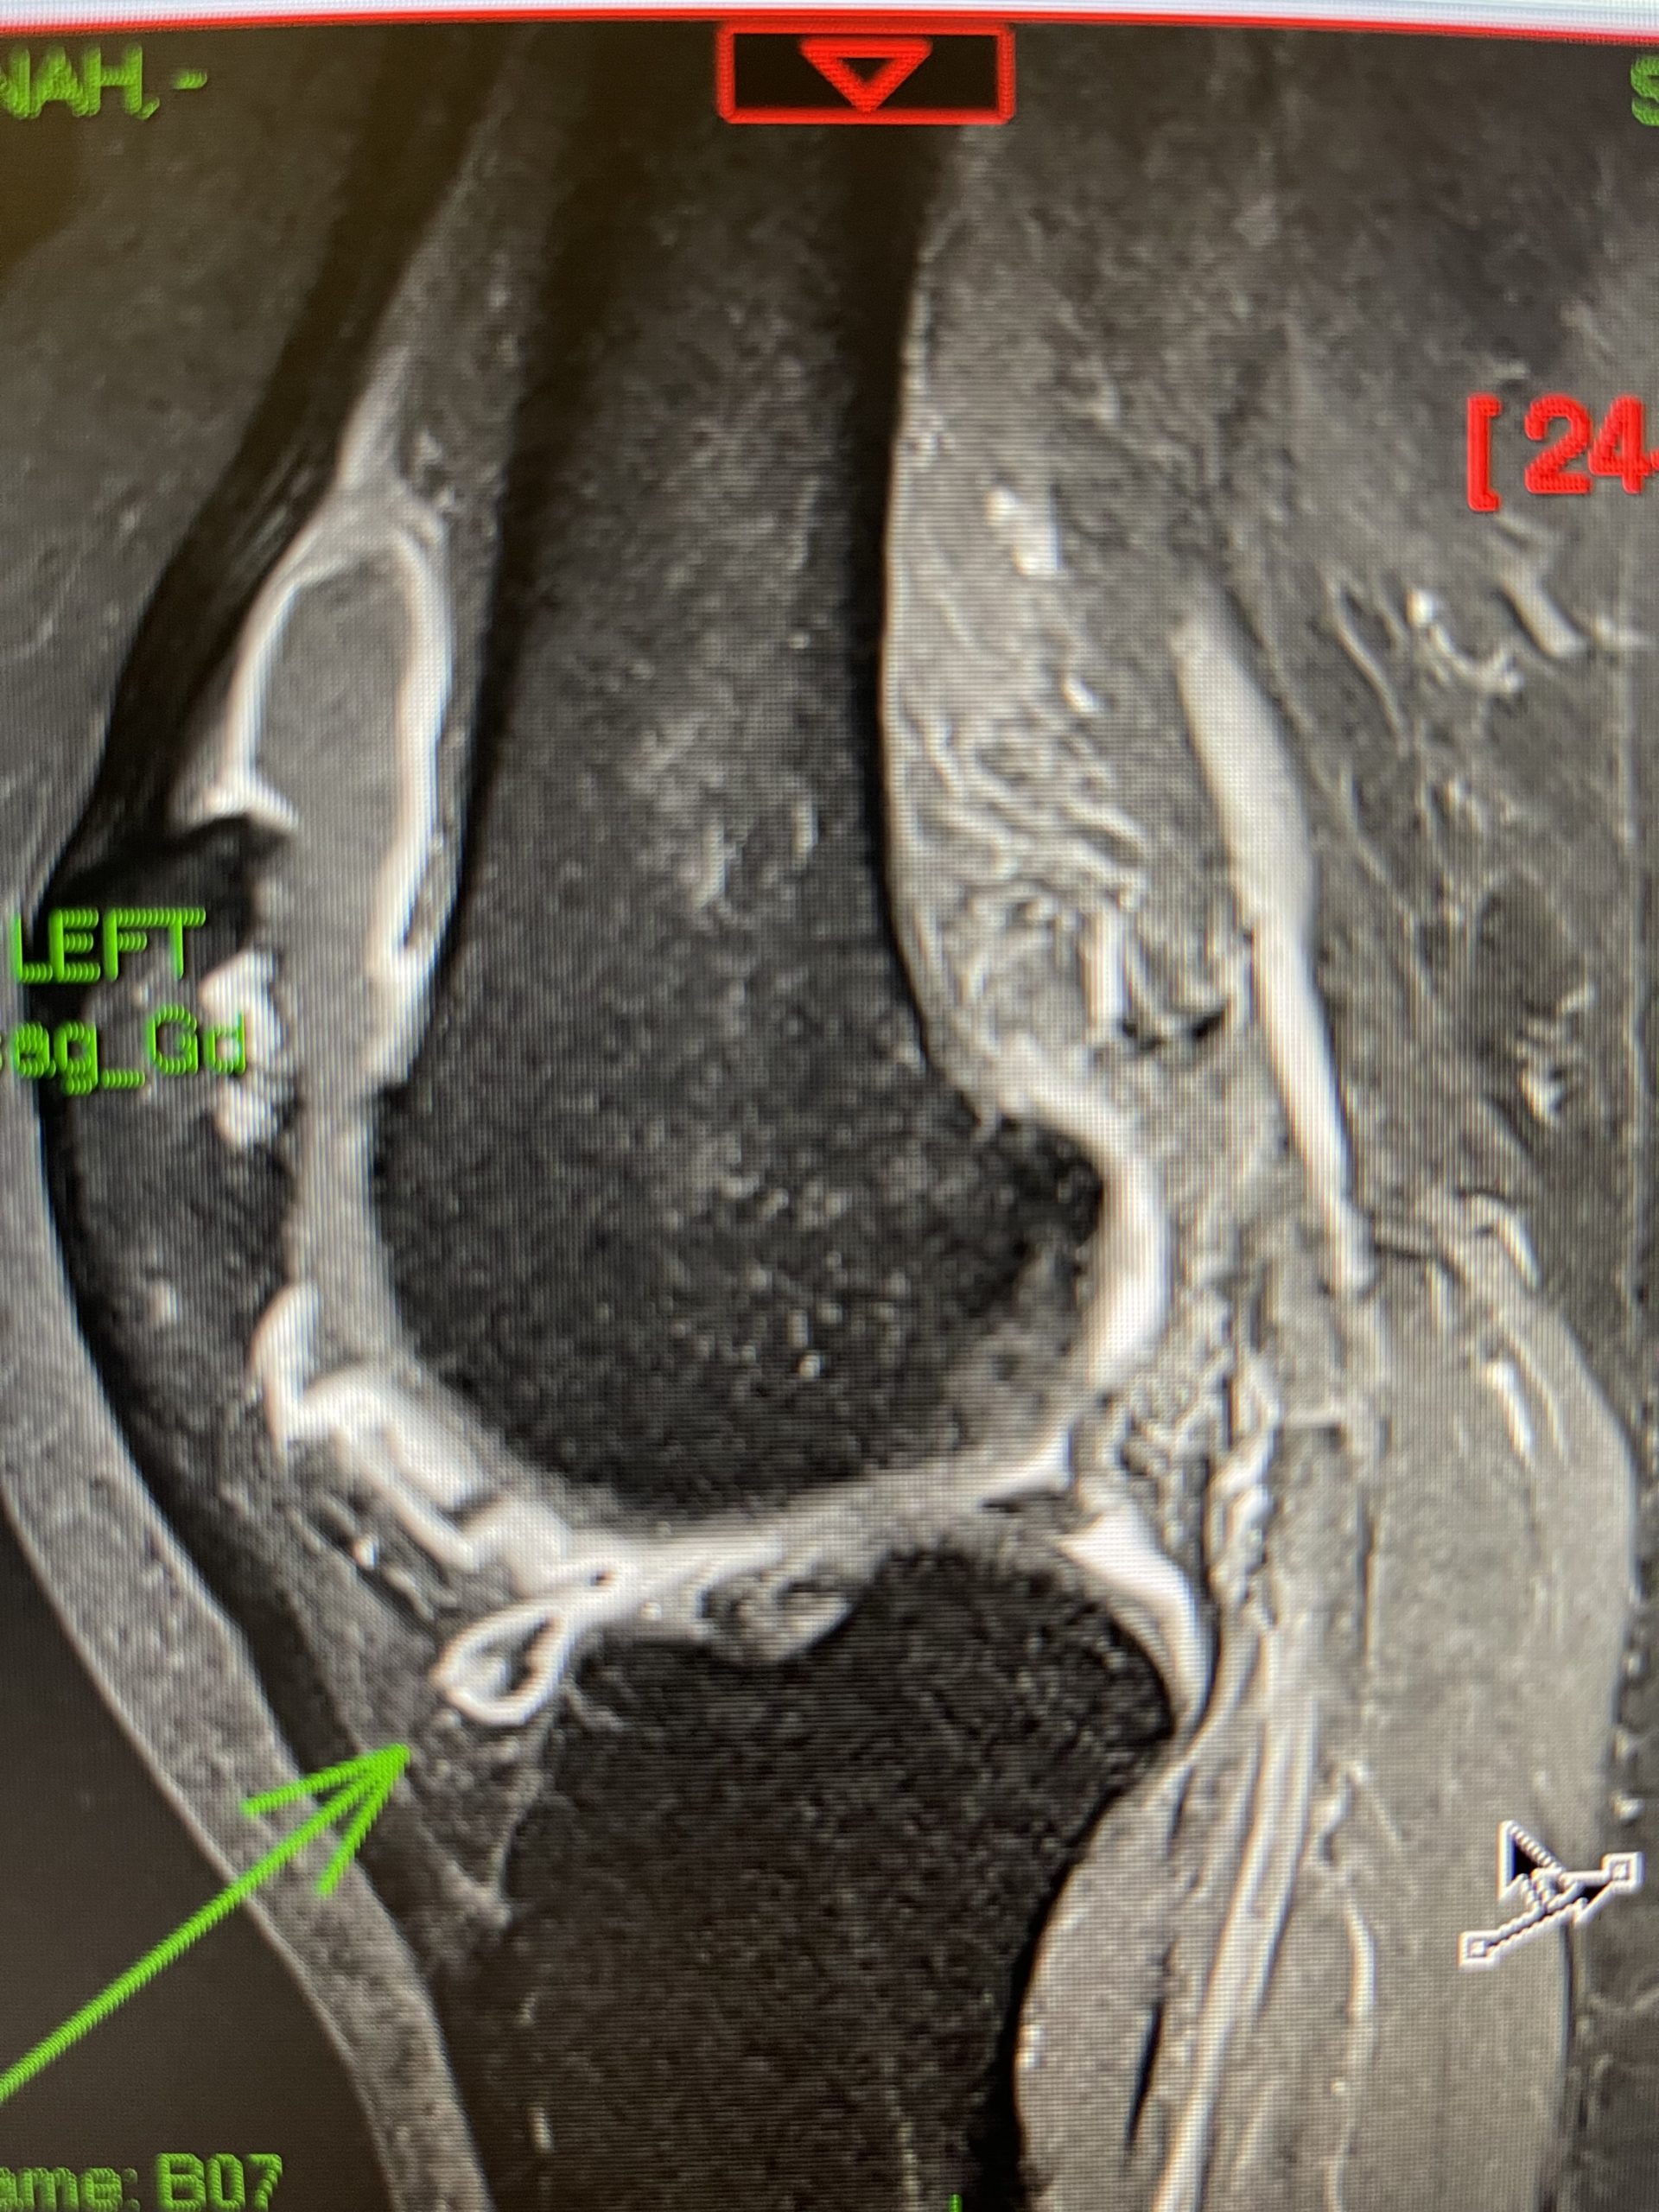

IMG_1753.jpeg